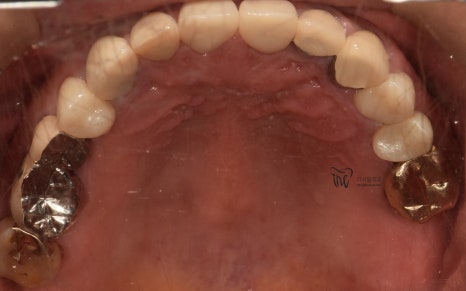

일단 사진에서 볼 수 있는 범위까지는,

한국에 계신 기간동안 열심히 치료해서

많은 변화를 안겨다 드렸었습니다.

그리고, 지르코니아 크라운을 연결해드리면서

결손부위에 따른 재건은 모두 마쳐드렸습니다.